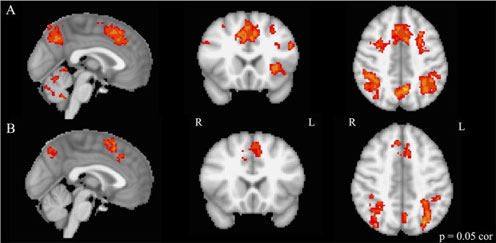

MRI scans show brain activation during executive functioning testing. The top row, row A, is of musically trained children. The bottom row, row B, is of untrained children. There’s more activation in the musically trained children. (Courtesy Nadine Gaab)

To find out, researchers gave complex executive functioning tasks to both musically trained and untrained children while scanning their brains in MRI machines.

While noting the children’s ability to follow the rules, the scientists also watched for activity in the prefrontal cortex of the brain, known to be the seat of executive functioning.

“We were just looking at how much of the prefrontal cortex was activated while they were doing this ‘neigh-froggy’ task in the scanner,” Gaab says. “And we could show that musically trained children and professional adult musicians have better executive functioning skills compared to their peers who do not play a musical instrument. We could further show that children who are musically trained have more activation in these prefrontal areas compared to their peers.”